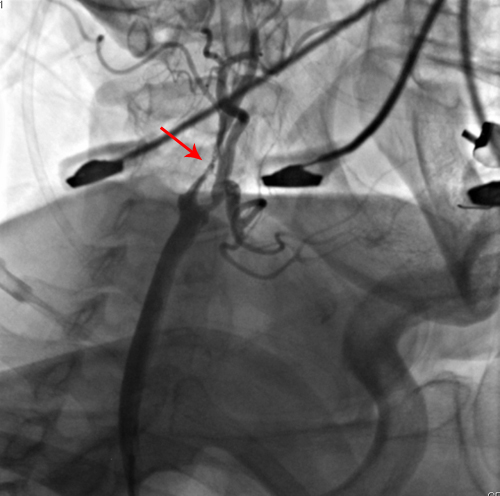

颈动脉CTA:左侧颈内、颈外动脉轻度狭窄,右侧颈外动脉、左锁骨下动脉起始段中度狭窄,右侧颈内、右锁骨下动脉起始段重度狭窄,右侧椎动脉重度狭窄。

该患者为老年女性,双侧颈动脉狭窄,且右侧为重度,患者反复间断头晕,肢体乏力1年余,有脑梗塞病史10年,高血压病5年,高脂血症3年,疑似冠心病,为脑卒中高危人群,且狭窄程度符合CEA手术标准,故予以手术治疗。2011年4月27日,协作组张勤奕教授顺利为其实施了右侧颈内动脉CEA。